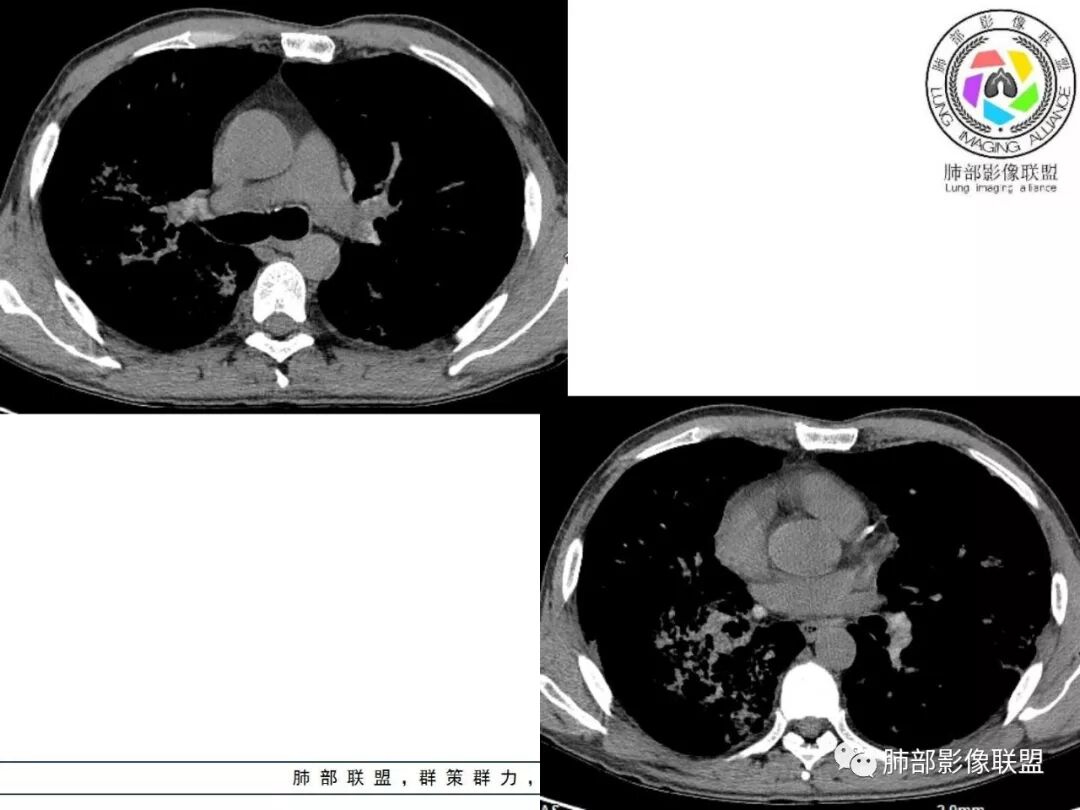

胸部CT:两肺弥漫病灶,磨玻璃影,少许实变,部分累及胸膜,磨玻璃区可见囊?少许胸腔积液,两肺可见结节,支气管血管束增粗,小叶间隔增厚,支气管走形有扭曲扩张,可见纤维化。气肿、大泡。考虑:感染性病变,PCP?查下HIV,CD4,G等。鉴别结核、结缔组织病肺浸润。

中年男性,亚急性病程,发热黄痰,c反应高;CT:分布胸膜下,支气管血管束周围,中上肺为主;磨玻璃、牵拉支扩,气管支气管粗,纵隔窗肺门淋巴结密度高;考虑:1)OP伴感染;2)巨气管支气管症;鉴别其他引起淋巴系统增殖性疾病如TB、NTM、淋巴瘤,当然有钙化,似乎淋巴瘤不太支持,需要进一步完善检查

从内科的角度一点不意外,而且病史采集很到位,午后低热,同时出现心包和胸腔积液,常见病中,最可能是结核和转移。前面说过,其他一些征象也支持结核。

弥漫性间质疾病,还伴心包,胸腔积液的,肺水肿也有可能,但临床不符,没有胸闷气急。

2. 肺气肿背景(小叶中心性肺气肿);双肺多发病灶整体沿血管支气管束及胸膜下分布,以上叶及下叶背段分布为主,有实变及GGO,边界清楚,有树芽,小叶间隔及中央间质增厚,叶间裂见到多发结节,部分支气管不规则牵拉扩张,提示病灶纤维化明显,结合临床病史,考虑病灶为间质性感染,肺门及纵隔内有钙化淋巴结,小叶间隔结节,考虑淋巴道增值性疾病可能,综合常规要怀疑间质性肺结核。